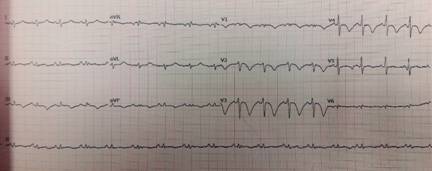

A su ingreso a urgencias, se encontró con TA 100/60 mmHg, FC 100 lpm; FR 35 r/min; oximetría de 80% al aire ambiental; cuello sin plétora yugular, campos pulmonares con estertores finos en ambas regiones infraescapulares; área precordial con ruidos cardiacos rítmicos, aumentados en frecuencia, con soplo regurgitante en mesocardio I/IV, sin irradiaciones ni galope; extremidades sin edema o signos de insuficiencia venosa superficial o profunda, pulsos y llenado capilar normales. El electrocardiograma mostró taquicardia sinusal y ondas T negativas de amplio voltaje en derivaciones precordiales V1 a V4 y en derivaciones inferiores (Figura 1). Con sospecha clínica de tromboembolia pulmonar (TEP), se solicitó dímero D, que reportó 5,000 u/L. Se estratificó al paciente en la escala de Wells modificada1 como de riesgo alto de TEP, por lo que se procedió a heparinización. El ecocardiograma transtorácico demostró dilatación importante de cavidades derechas, disfunción contráctil del ventrículo derecho y presión sistólica de la arteria pulmonar de 50 mmHg (Figura 2). Se efectuó angiotomografía pulmonar, que registró TEP submasiva con 45% de obstrucción de acuerdo al índice de Qanadli2 (Figura 3) y angiotomografía para valorar circulación venosa a nivel iliofemoral, donde se encontró trombosis venosa profunda izquierda (Figura 4). El grupo de respuesta para embolia pulmonar (PERT) decidió efectuar una trombólisis mediante sistema endovascular Eko-Sonic con acceso femoral derecho y administración de activador del plasminógeno humano recombinante/rt-PA, en infusión, utilizando una dosis de 10 mg en bolo inicial tanto en arteria pulmonar mediante el sistema mencionado como en vena iliaca mediante catéter multifenestrado intratrombo por vía percutánea con abordaje en vena poplítea ipsilateral; se prosiguió con aplicación de trombolítico a 0.5 mg/hora por 15 horas en la arteria pulmonar y vena iliaca izquierda, suspendiéndose en dicho momento por presencia de hemoptisis. La dosis total de alteplase fue de 35 mg. La evolución fue progresivamente hacia la mejoría; el ecocardiograma de control documentó disminución significativa de la presión arterial pulmonar y reducción en el tamaño de las cavidades derechas; la angiotomografía pulmonar de control demostró descenso en la carga de trombo en ambas ramas pulmonares y la vena iliaca.

Figura 1: Electrocardiograma de 12 derivaciones el día del ingreso, en donde destaca la presencia de ondas T negativas de alto voltaje en derivaciones precordiales V1 a V4, que expresan importante sobrecarga sistólica del ventrículo derecho.